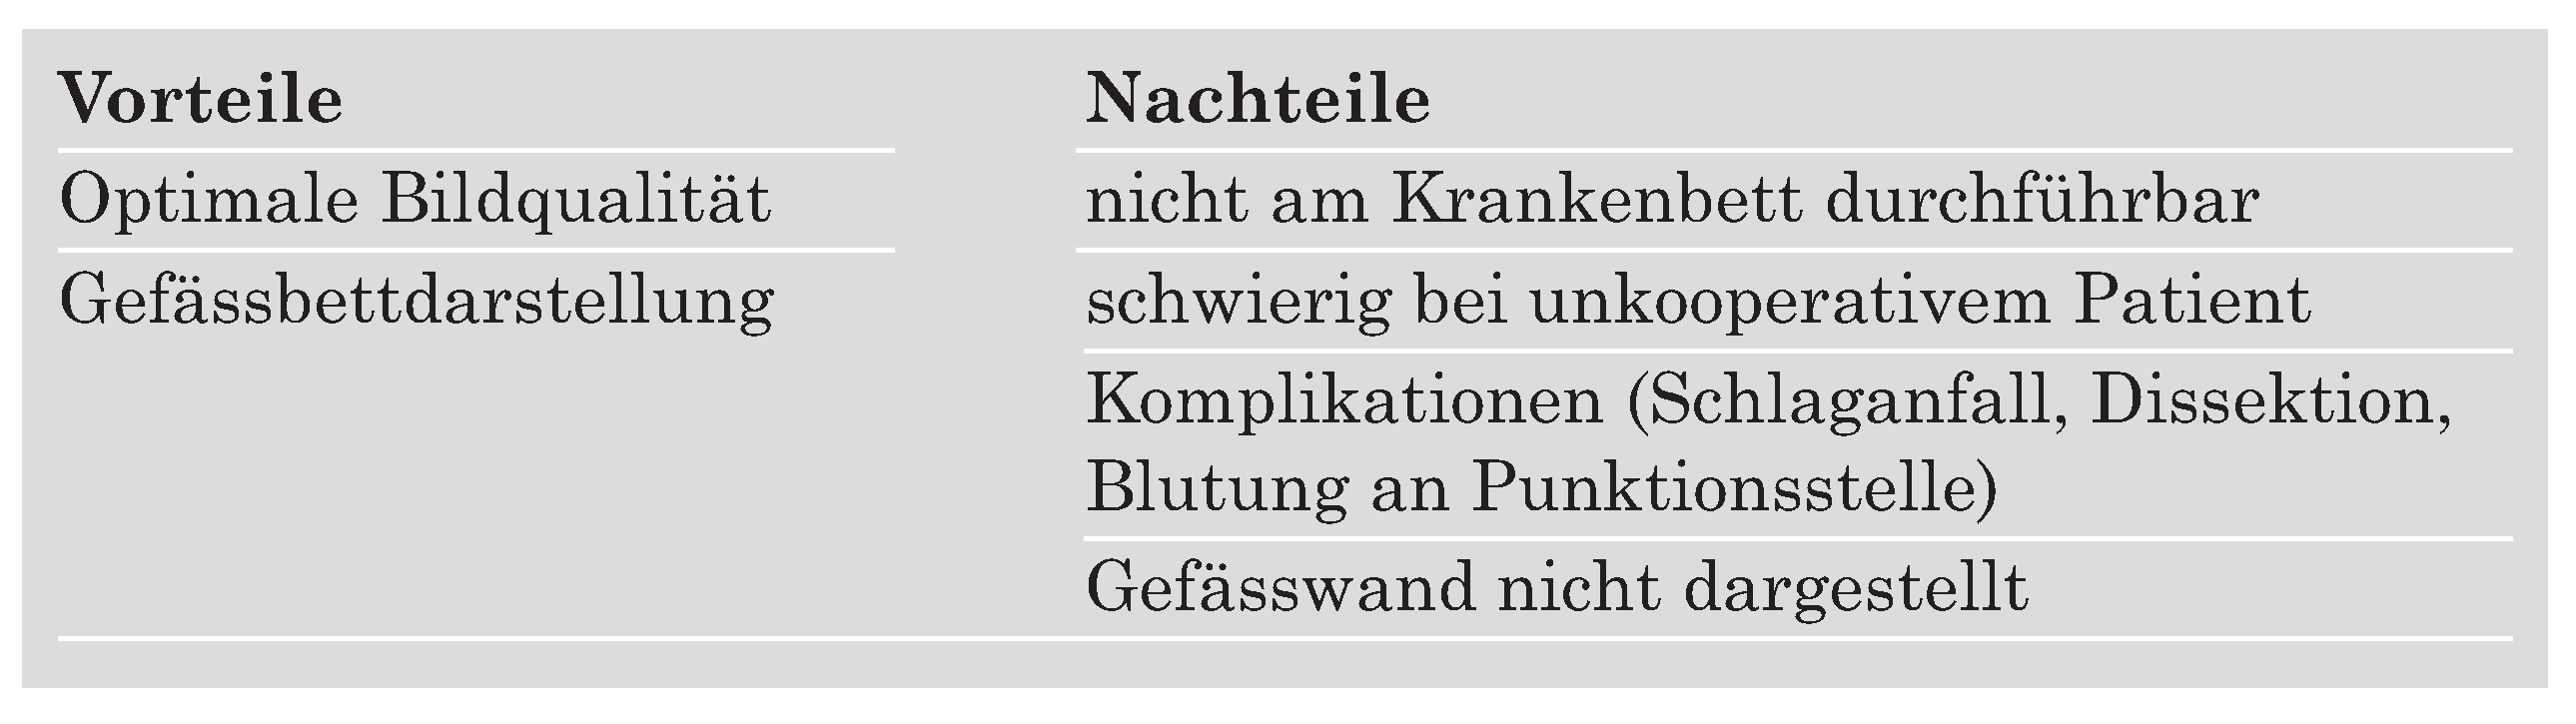

Die Katheter-Angiographie